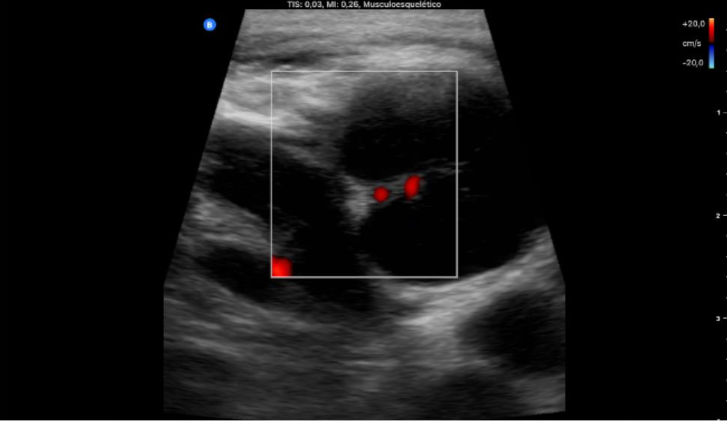

Objetivación de conglomerado adenopático con 2 adenopatías predominantes redondas de 2 cm, bien delimitadas, con hilio periférico y vascularización en hilio. Tiroides normal, bazo e hígado normales sin LOEs.

Uso de sonda lineal, proyección transversal: adenopatía redondeada con hilio periférico bien delimitada que no capta Doppler; y longitudinal: varias adenopatías, 2 de ellas más grandes, donde se objetiva la vascularización limitada al hilio.